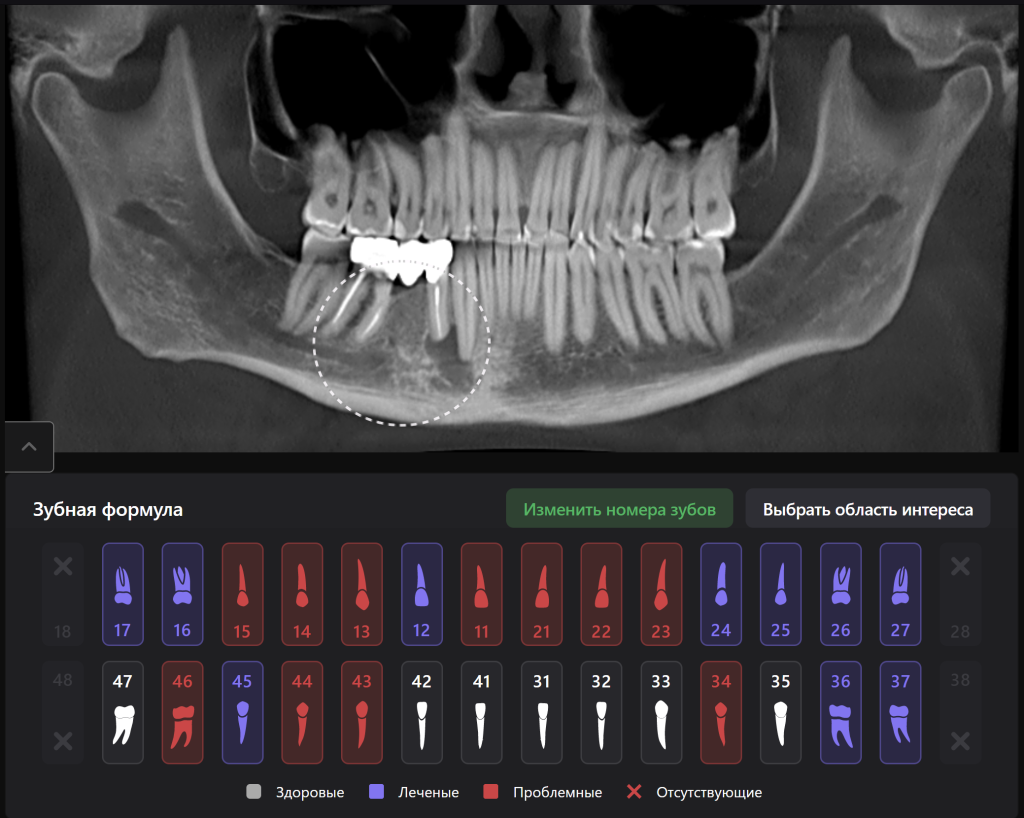

Рентгенологический отчет Diagnocat не только указывает на наличие периапикального участка деструкции, но и указывает на его причины – наличие незапломбированного канала

«Эндодонтический отчет» Diagnocat помогает зафиксировать изначальный объем периапикального очага и изучить анатомию и морфологию корневых каналов до начала лечения